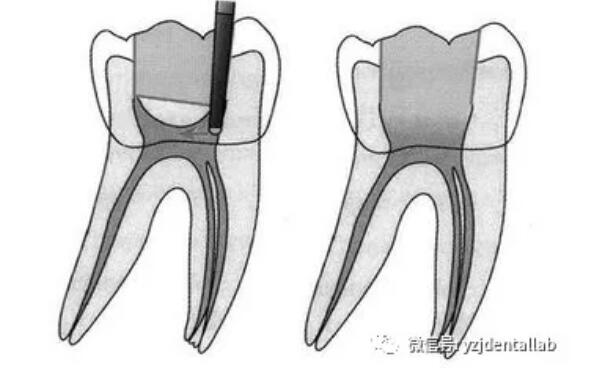

根管治疗术是医生用根管治疗专用器械通过彻底去除感染的牙髓以及感染的牙本质和毒性分解产物,经过根管冲洗、消毒和严密填塞根管,隔绝细菌进入根管再感染,防止根尖周病变的发生或促进根尖周病的愈合。

、开髓去腐质

去净腐质和原有充填物、揭净随顶,看到整个髓底解剖结构、髓壁与根管壁连续流畅、没有牙颈部台阶,没有过度切割髓壁和髓底以便后续治疗顺利进行。

开髓步骤:

局麻--上橡皮障--去除所有腐质--接髓顶--形成与根尖孔1/3的直线。